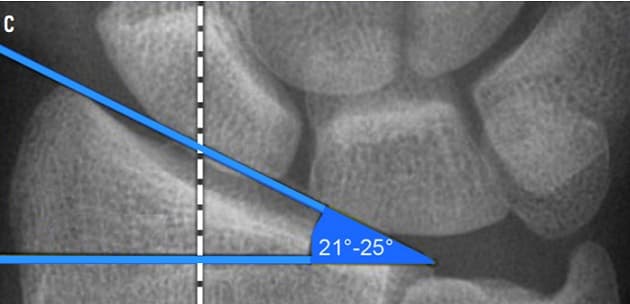

The objective of this study was to evaluate whether volar locking plating can restore the anatomical volar tilt of 12° and the anatomical length of the radius relative to the ulna. We retrospectively reviewed the radiographic outcome of distal radius fractures treated with two different first-generation locking plate systems; VariAx (Stryker) and Acu-Loc (Acumed).